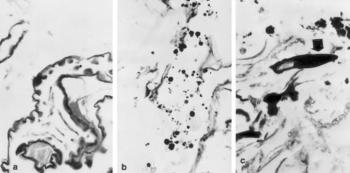

119. ábra. a) Cérnagiliszta (Enterobius vermicularis) részlete b) Féregpeték a béltartalomban c) Más fajhoz tartozó, de nem azonosítható bélféreg rostellumai 19. század, 40 éves férfi. Pikrosziriusz-festés, 150× nagyítás

Az emberi bélférgesség epidemiológiájára vonatkozó adatok akkor szaporodtak meg, amikor rájöttek, hogy a szemét- és pöcegödrök anyagában, továbbá a csontvázak medencéjéből vett földben kimutathatók a féregrészek (Fry és Moori 1969). A talajmintákból Enterobius vermicularis, Diphyllobotrium pacificum (Araujo és mtsai 1983), Strongyloides stercoralis, Ascaris lumbricoides (Reinhard és mtsai 1988) petéjét azonosították. A H. sapiens sapiens, de talán már a neandervölgyi ember is szenvedett bélférgességben. A trópusi és szubtrópusi vidékeken és az állattenyésztők körében gyakoribb, a mérsékelt és hideg égövi területeken valamivel ritkább volt a helminthiasis (Wells 1984/85). Hazánkban elsőként Tóth (1996) ismert fel Taenia petéket a gyermek medencéjéből vett földmintában. A váci múmiák közül a 36 éves korában elhunyt pap-tanár spontán mumifikálódott tetemének béltartalmából sem flotációs, sem szedimentációs eljárással féreg részeket nem találtak, a vékonybél szövettani vizsgálata a parazita testének részeit és petéit megtalálta (119. ábra). A gyermekközösségben élt férfi valószínűleg cérnagiliszta (Enterobius vermicularis) fertőzésben szenvedett (Józsa és Pap 2000).